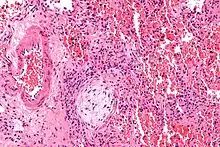

| Micrograph showing a Masson body (off center left/bottom of the image – pale circular and paucicellular), as may be seen in cryptogenic organizing pneumonia. The Masson body plugs the airway. The artery associated with the obliterated airway is also seen (far left of the image). H&E stain. | |

Organizing pneumonia is usually preceded by some type of lung injury that causes a localized denudation or disruption in continuity of the epithelial basal laminae of the type 1 alveolar pneumocytes that line the alveoli.[9] This injury to the epithelial basal lamina results in inflammatory cells and plasma proteins leaking into the alveolar space and forming fibrin, resulting in an initial fibroblast driven intra-alveolar fibroproliferation.[9] The fibroblasts differentiate into myofibroblasts and continue to form fibrosis resulting in intra-alveolar fibroinflammatory buds (Masson's Bodies) that are characteristic of organizing pneumonia.[9] These Masson's bodies consist of inflammatory cells contained in an extracellular matrix consisting of type I collagen, fibronectin, procollagen type III, tenascin C and proteoglycans.[9] Angiogenesis , or the formation of blood vessels, occurs in the Masson's bodies and this is driven by vascular endothelial growth factor.[9] Remodeling occurs, resulting in the intra-alveolar fibroinflammatory buds (Masson's Bodies) moving into the interstitial space and forming collagen globules that are then covered by type 1 alveolar epithelial cells with well developed basement membranes. These type 1 alveolar epithelial cells (pneumocytes) then proliferate, restoring the continuity and function of the alveolar unit.[9] This process is in contrast to the histopathologic changes seen in usual interstitial pneumonia where extensive fibrosis and inflammation occur leading to fibroblastic foci to form in the alveolar spaces resulting in obliteration of the alveolar space, scarring and significant damage to lung architecture (the alveoli).[9]

Histologically, cryptogenic organizing pneumonia is characterized by the presence of polypoid plugs of loose organizing connective tissue (Masson bodies) within alveolar ducts, alveoli, and bronchioles.